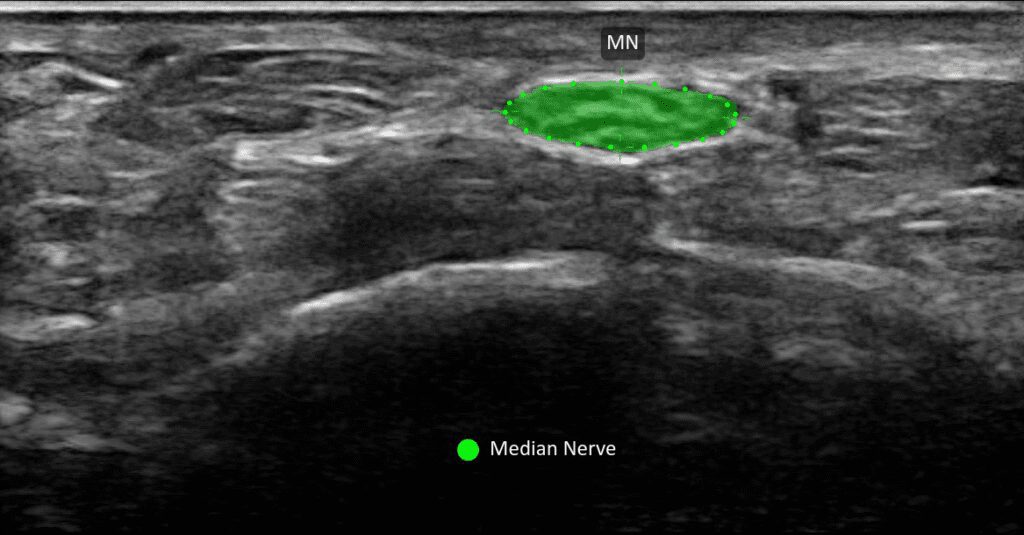

You can carry it from office to office, put it in your lab coat and use it on pain rounds. The image quality is superior.

It’s very easy to hold. You can scan for a good long time and really not get tired because it’s so lightweight and compact.